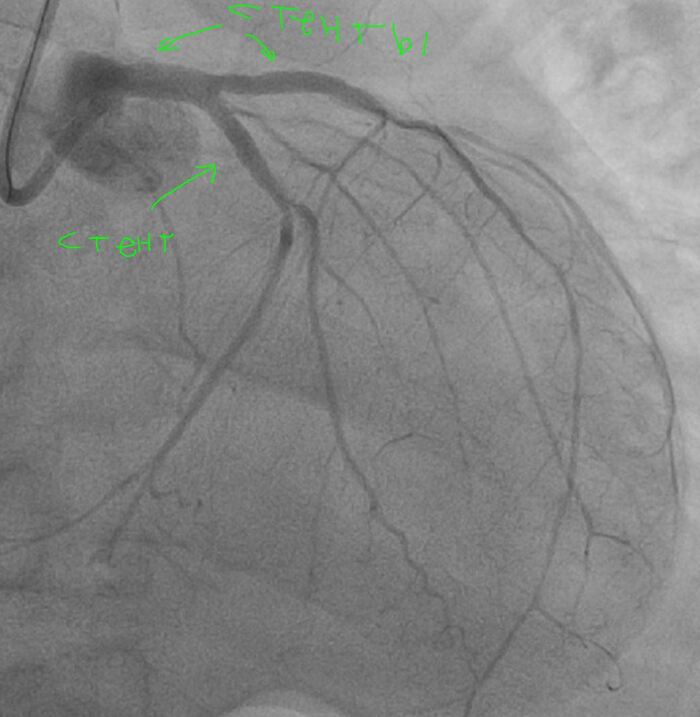

С учетом данных ВСУЗИ проводится сразу прямое (без предварительной предилатации баллоном) стентирование ПМЖА с покрытием ствола левой коронарной артерии.

Получаем такой результат